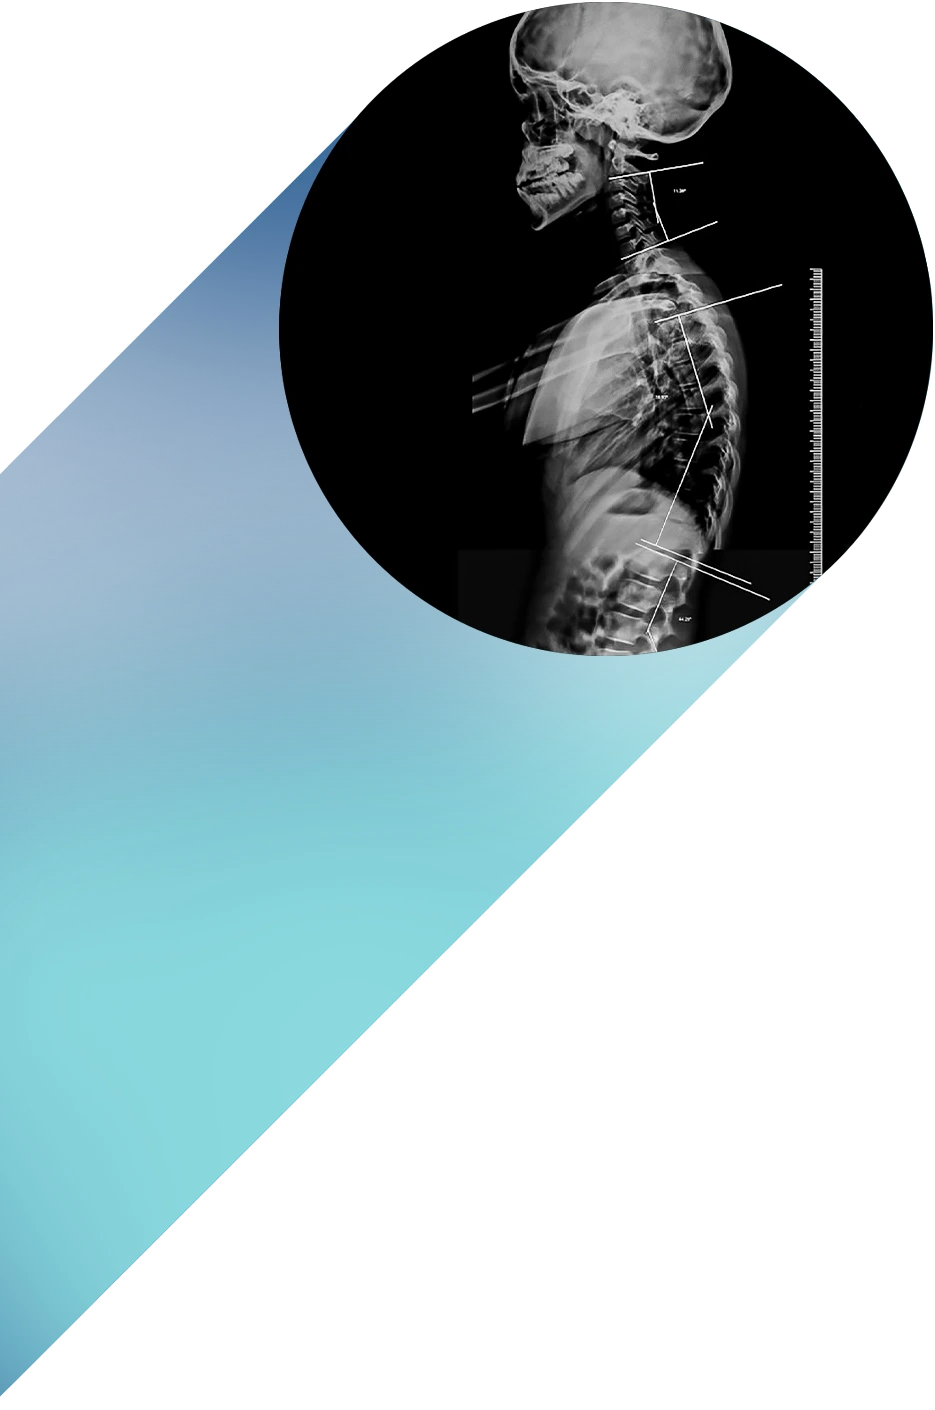

Nuestro compromiso ha sido, y sigue siendo, ofrecer estudios de máxima precisión con la tecnología más avanzada del país: Resonancia Magnética 3 Teslas con Inteligencia Artificial, Tomografía Multicorte de última generación, Radiografía digital, Mamografía digital y Ecografía de alta resolución.

Imágenes nítidas en segundos, con menor radiación y máximo detalle para detectar fracturas, enfermedades pulmonares, lesiones dentales, neoplasias y metástasis óseas. Incluye protocolos Full Spine y Long Leg para diagnósticos ortopédicos avanzados.